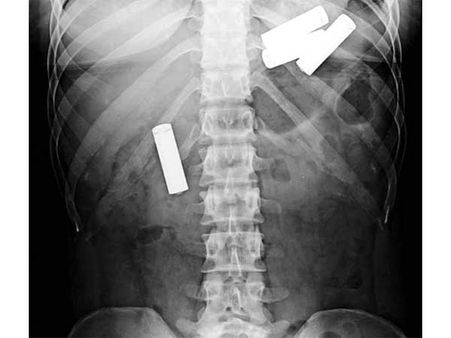

ખિલ્લી

ચીનના એક કાર્પેન્ટર દ્વારા ભૂલથી એક ખીલ્લી ગળાઇ ગઇ. તેના મોઢામાં ખીલ્લી હતી અને તેને ખાંસી આવી અને તે ગળાઇ ગઇ. એટલું જ નહીં આ ખિલ્લી તેના ફેંફસામાં અટકી ગઇ. જો કે ભારે મહેનત બાદ સર્જરીથી તેને દૂર કરવામાં આવી.